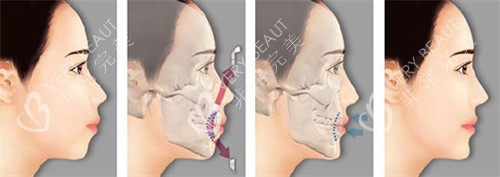

第7天:消肿30%左右,终于能看清轮廓变化——下颌线条后缩了!

***个月:摘掉咬合板,练习张嘴训练。惊喜发现牙齿能自然闭合了!

第3个月:啃苹果、嚼牛肉都不再费力,妈妈笑着说:“你吃饭声终于不吓人了。”

第6个月:复诊拍片显示骨骼愈合良好。何医生指着侧脸对比图说:“现在这弧度才符合美学标准。”

现在照镜子时,我总会想起分享在北京联合丽格做双鄂整形的经历时,何医生那句话:“医疗美容的本质是医疗,美只是健康的副产品。”的确,咬合改善后,发音更清晰、睡眠呼吸更顺畅,这些“隐形收获”比变漂亮更让我感动。